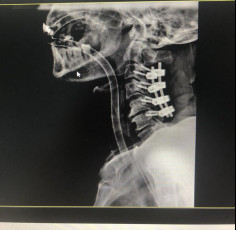

(術(shù)后拍片)

治療效果顯著康復(fù)出院

今年5月,張阿伯出院近2月后,大部分生活已經(jīng)可以自理。戈主任為張阿伯做了復(fù)查診治,結(jié)果顯示他的頸椎固定可靠,復(fù)位良好,病體正在朝理想的康復(fù)方向發(fā)展。